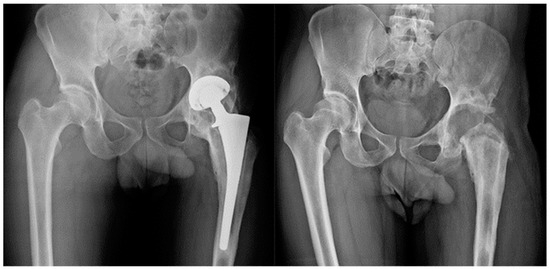

The same procedure was performed in all patients. Patients were explanted and antibiotic therapy was subsequently set up, at first empiric, and then targeted for the isolated pathogen. In no case were antibiotic spacers used. The antibiotic therapy was administered according to the culture sensitivity results. Antibiotic therapy was performed until normalization of CRP following explantation and, in any case, never for more than 8 consecutive weeks. One year after resection arthroplasty was performed, the following two possible outcomes were evaluated: successful TSE arthroplasty was performed in 14 patients (Group A) (Figure 1), and resection arthroplasty without reimplantation in 7 (Group B) (Figure 2). The following were the replanting criteria: CRP normalization with antimicrobial treatment in at least two controls separated by two weeks. If normalized, antibiotic therapy was discontinued, patients were then monitored for an additional 4 weeks by weekly CRP checks. If the latter remained normal, labeled leukocyte scintigraphy was done. If the latter was also negative, reimplantation was scheduled, which was to be performed only after intraoperative negative histology.

Figure 2.

Group B. Patient with communicating sinus tract at the diagnosis. After ex-plantation and targeted antimicrobial therapy for a polymicrobial PJI, the patient was not considered eligible for reimplantation.